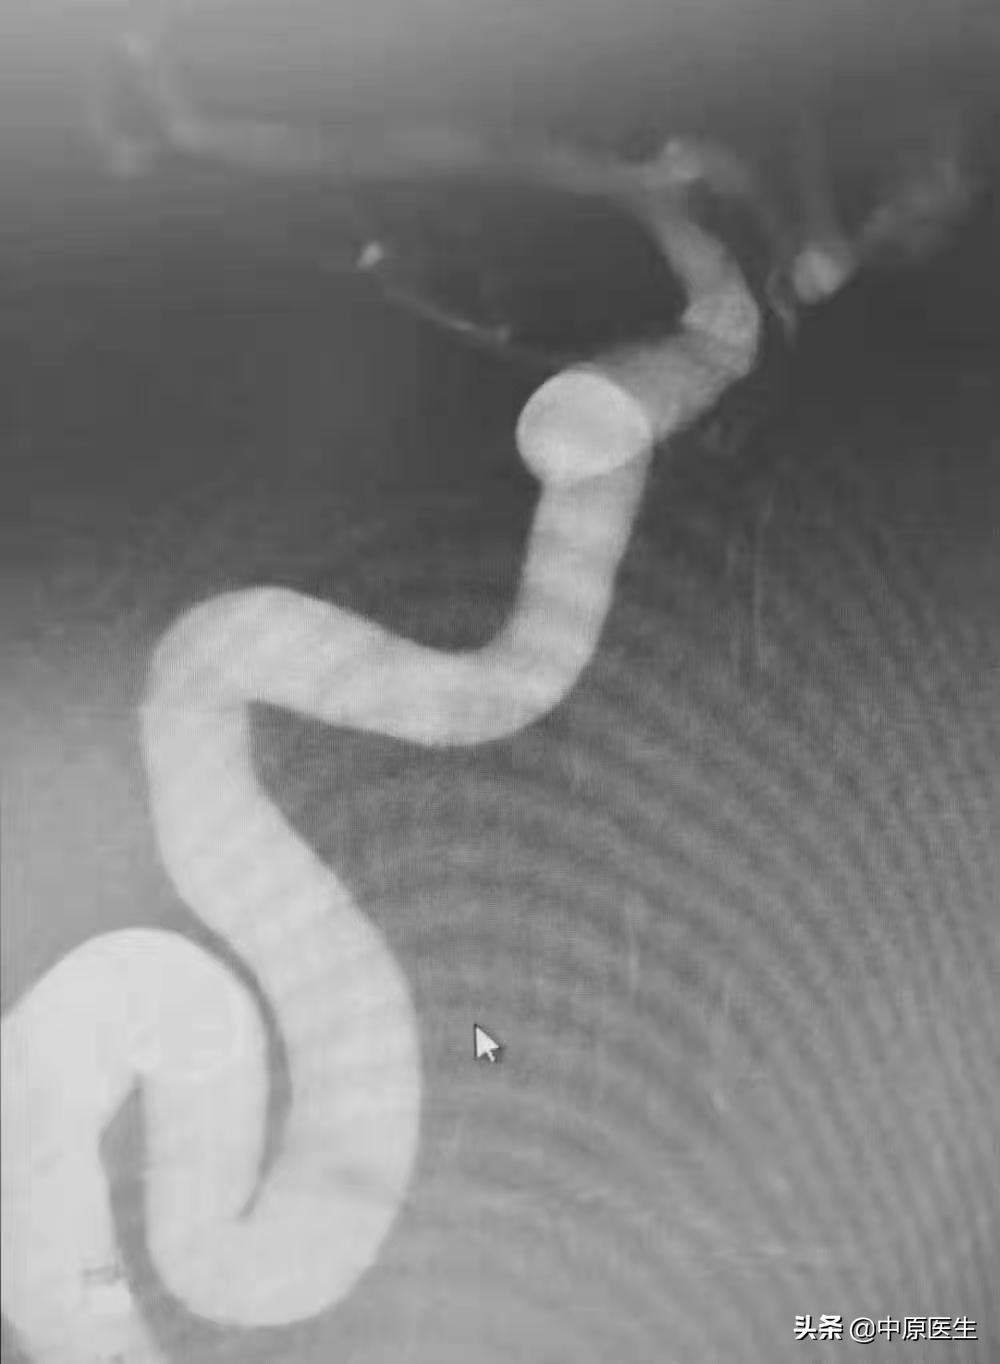

一个老人体检大脑里发现两个动脉瘤,(见图1)然后来看我的门诊。

血管曲里拐弯儿,可把赵小源难为坏了。(见图2~6)